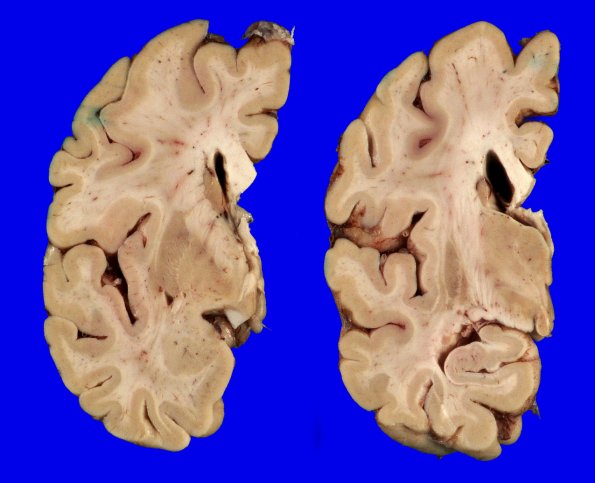

Coronal slicing revealed mild dilatation of the left lateral ventricle and its inferior horn, indicating mild loss of brain parenchyma. The hippocampus appeared macroscopically of normal size and proportion. ---- Final Neuropathologic Diagnoses: Diffuse Lewy body disease (Parkinson disease with dementia; brainstem, limbic and neocortical); Alzheimer's disease neuropathologic change (Low: A3, B1, C1). ---- Comment: This case displays alpha-synuclein-positive inclusions in the form of Lewy bodies and Lewy neurites in brainstem, limbic and neocortical areas. When AD and DLBD are seen in one patient, as here, there is a ‘high probability’ that the Lewy body pathology contributed to the dementia (McKeith et al, PMID: 16237129).